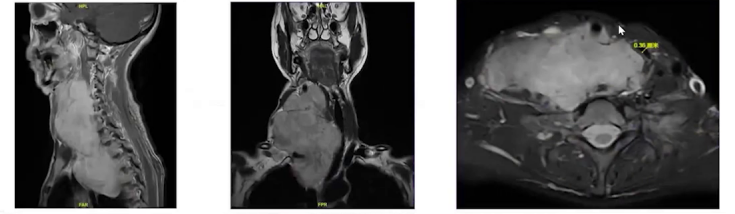

我院核磁共振检查发现,这是一个从颈部延伸至纵隔的巨大肿物,上下径达16cm,压迫甲状腺、气管、上腔静脉、右锁骨下动脉、右椎动脉及右颈总动脉等,气管最狭窄处直径不到4mm。